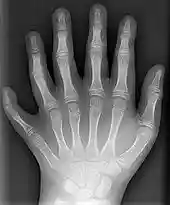

X-ray of human hand | |

![]()

X-ray of the left hand of a ten-year-old boy with polydactyly.

A number of genetic disorders affect the hand. Polydactyly is the presence of more than the usual number of fingers. One of the disorders that can cause this is Catel-Manzke syndrome. The fingers may be fused in a disorder known as syndactyly. Or there may be an absence of one or more central fingers—a condition known as ectrodactyly. Additionally, some people are born without one or both hands (amelia). Hereditary multiple exostoses of the forearm—also known as hereditary multiple osteochondromas—is another cause of hand and forearm deformity in children and adults.[20]